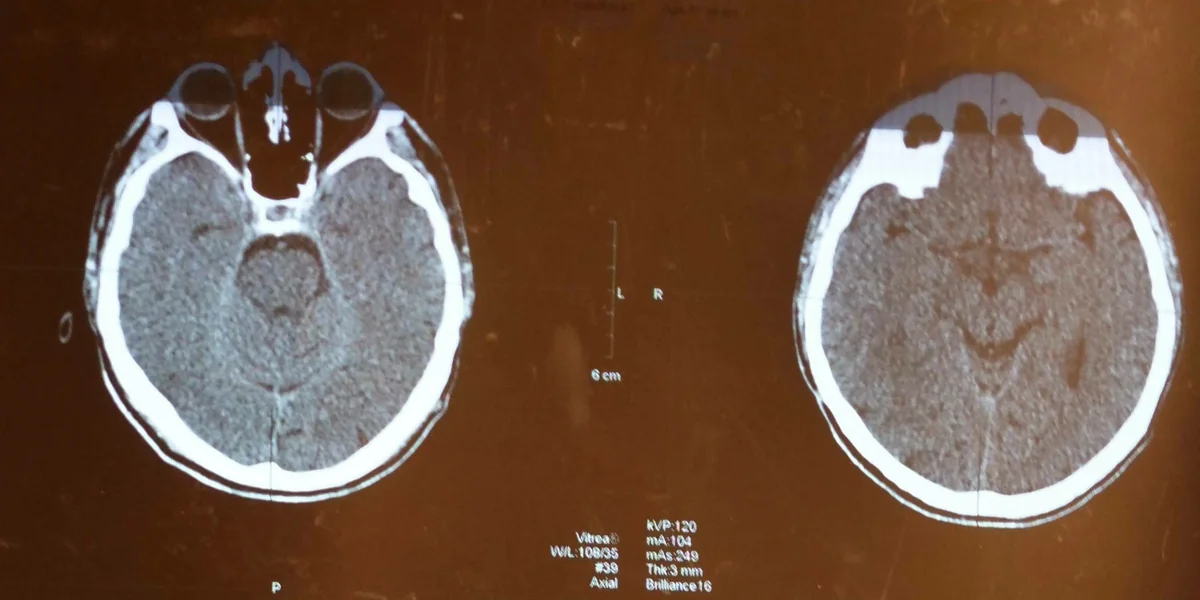

Auch das Gehirn kann von Krebs befallen sein. Die Behandlung muss dann besonders zielgerichtet erfolgen Foto: imago